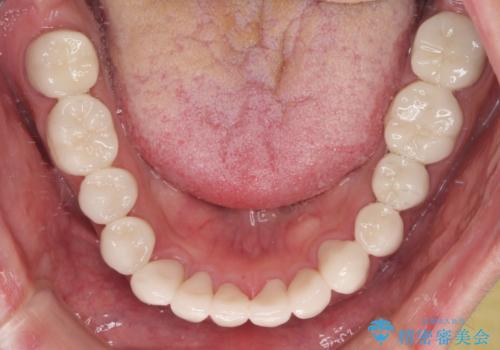

当初はむし歯処置が必要な歯のみの治療予定でしたが、捻転や咬み合わせを可及的に改善したいとのことで、全顎的にオールセラミッククラウンにて補綴治療を行うこととしました。

仮歯で過ごす期間を一定期間も受けることで徐々に変化になれていくようにし、オールセラミッククラウン装着時には違和感なく過ごすことができるようにしています。